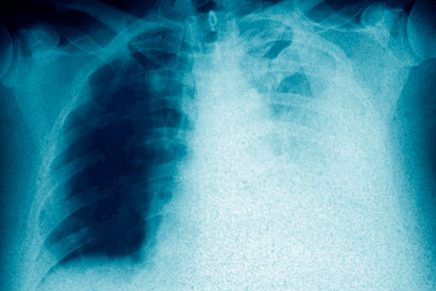

Finalmente, después de una endoscopia, procedimiento que tardó aproximadamente 10 minutos, fue extraído el utensilio metálico de 13 cm de largo, aproximadamente.